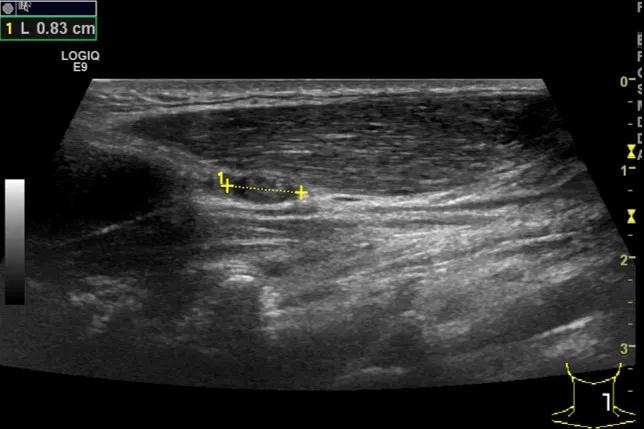

随后,徐栋教授进一步分享了五个临床实战病例,带来了更直观的热消融治疗经验。第一个病例是62岁肺癌患者,术后1年余发现双侧锁骨上淋巴结复发,侵犯神经,存在静脉回流、淋巴回流障碍,肿胀、疼痛非常明显。影像显示患者淋巴结边界不清、形态不规则,存在浸润,血流强化增强。由于患者在系统治疗后进展,且主要目的缓解症状、减瘤。局麻下行热消融术,从后向前逐层消融,热消融之后超声造影即刻评估显示完全充盈缺损,完全覆盖病灶。

(病例1图例)